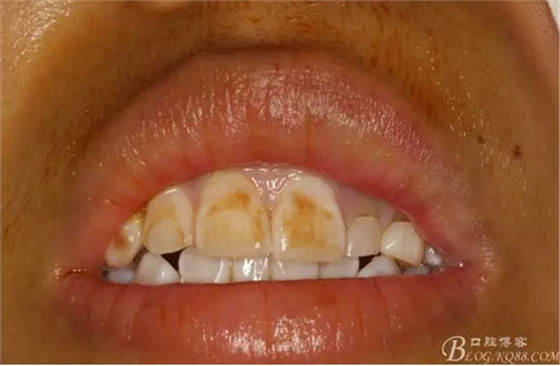

圖2.術(shù)前口內(nèi)像,左側(cè)乳Ⅱ、Ⅲ滯留,頸部楔形缺損,探針不敏感。左側(cè)乳Ⅱ、Ⅲ唇側(cè)粘膜膨隆,表面結(jié)節(jié)狀,捫診質(zhì)地堅(jiān)硬,無(wú)波動(dòng)。